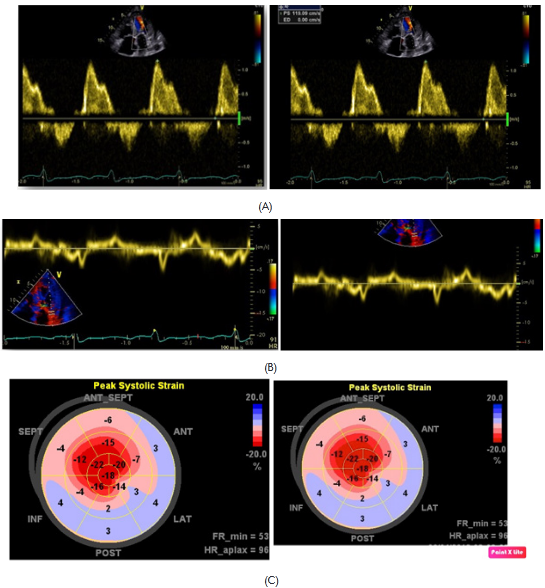

Subsequently, she was admitted to our institution with a clinic diagnosis of acute heart failure, Stevenson B. A chest X-ray showed bilateral pleural effusion, grade II. During the admission, the only significant finding was mild anemia (Hb 11,1g/dl). A transthoracic echocardiogram (Figure 1 & Video 1) was done showing normal left ventricle diameters, LV ejection fraction 47%, mild concentric hypertrophy, biatrial enlargement, mild to moderate mitral regurgitation, pseudo normal ventricular filling pattern, e 4cm/sec, E/e´ ratio greater than 18, moderate tricuspid insufficiency, an estimate pulmonary artery systolic pressure of 55mmHg and mild pericardial effusion. The presumptive diagnosis of infiltrative restrictive cardiomyopathy was assumed. A myocardial 3D strain imaging with speckle tracking was done, showing normal longitudinal strain of apical segments and a strong impaired values of basal and mid segments (-16 to -28 at apical segments vs 4 to -4 at basal level) (Figure 2C). The patient improved clinically with diuretics and vasodilators according to local guidelines. Nevertheless, during the third day of hospitalization she experiences a sudden death episode, with ventricular tachycardia documented in the telemetric system, with an adequate response to cardiopulmonary resuscitation (CPR).

Figure 2 diastolic mitral flows with pseudo normal pattern (A). E´ wave plainly decreased to the side mitral ring level (B). Global longitudinal strain with normal values at apical level and diminished in mid and basal segments (C).